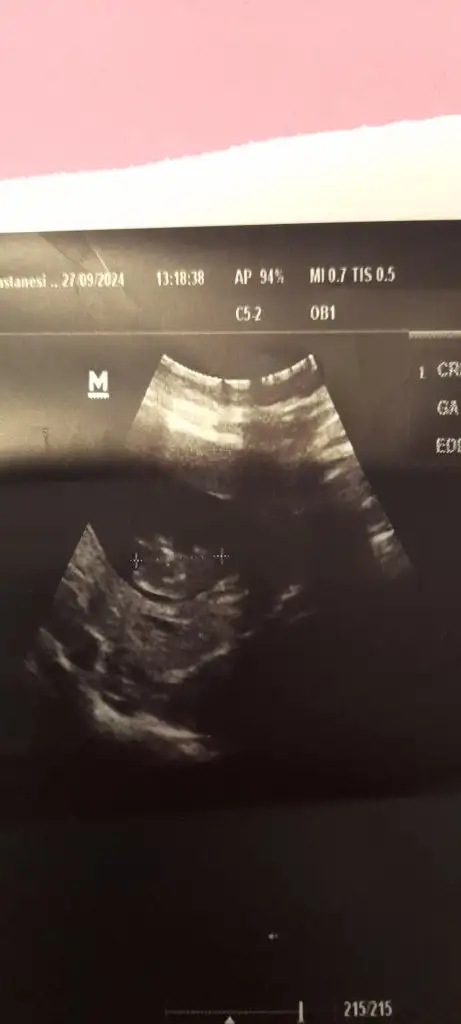

Karından hepsiBenimkinede bakar mısın rica edersem

7.haftada solda 8. Haftada sağda hangisi doğru şimdiRamzi teorisine göre ( bilimsel bir araştırma sonucuymuş ve %85 doğruluğu varmış). İlk 6-8 haftalık ultrason görüntüsüne göre bebeğin kesenin içersinde soldan ya da sağdan girişine göre cinsiyet tahmini yapılıyor. Bilimsel olunca tecrübeli annelerimiz yada anne adaylarımızdan yardım istiyoruz. Doğruluğu var mı öğrenmek adına :) Bizleri aydınlatırsanız çok seviniriz. bu teorieye göre;